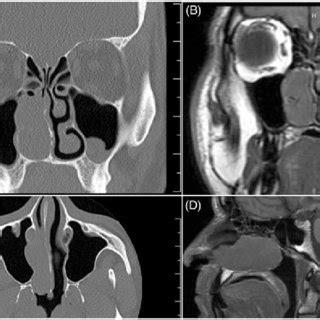

(A) Coronal computed tomography (CT) scan (bone window ...

(A) Coronal computed tomography (CT) scan (bone window ... from www.researchgate.net